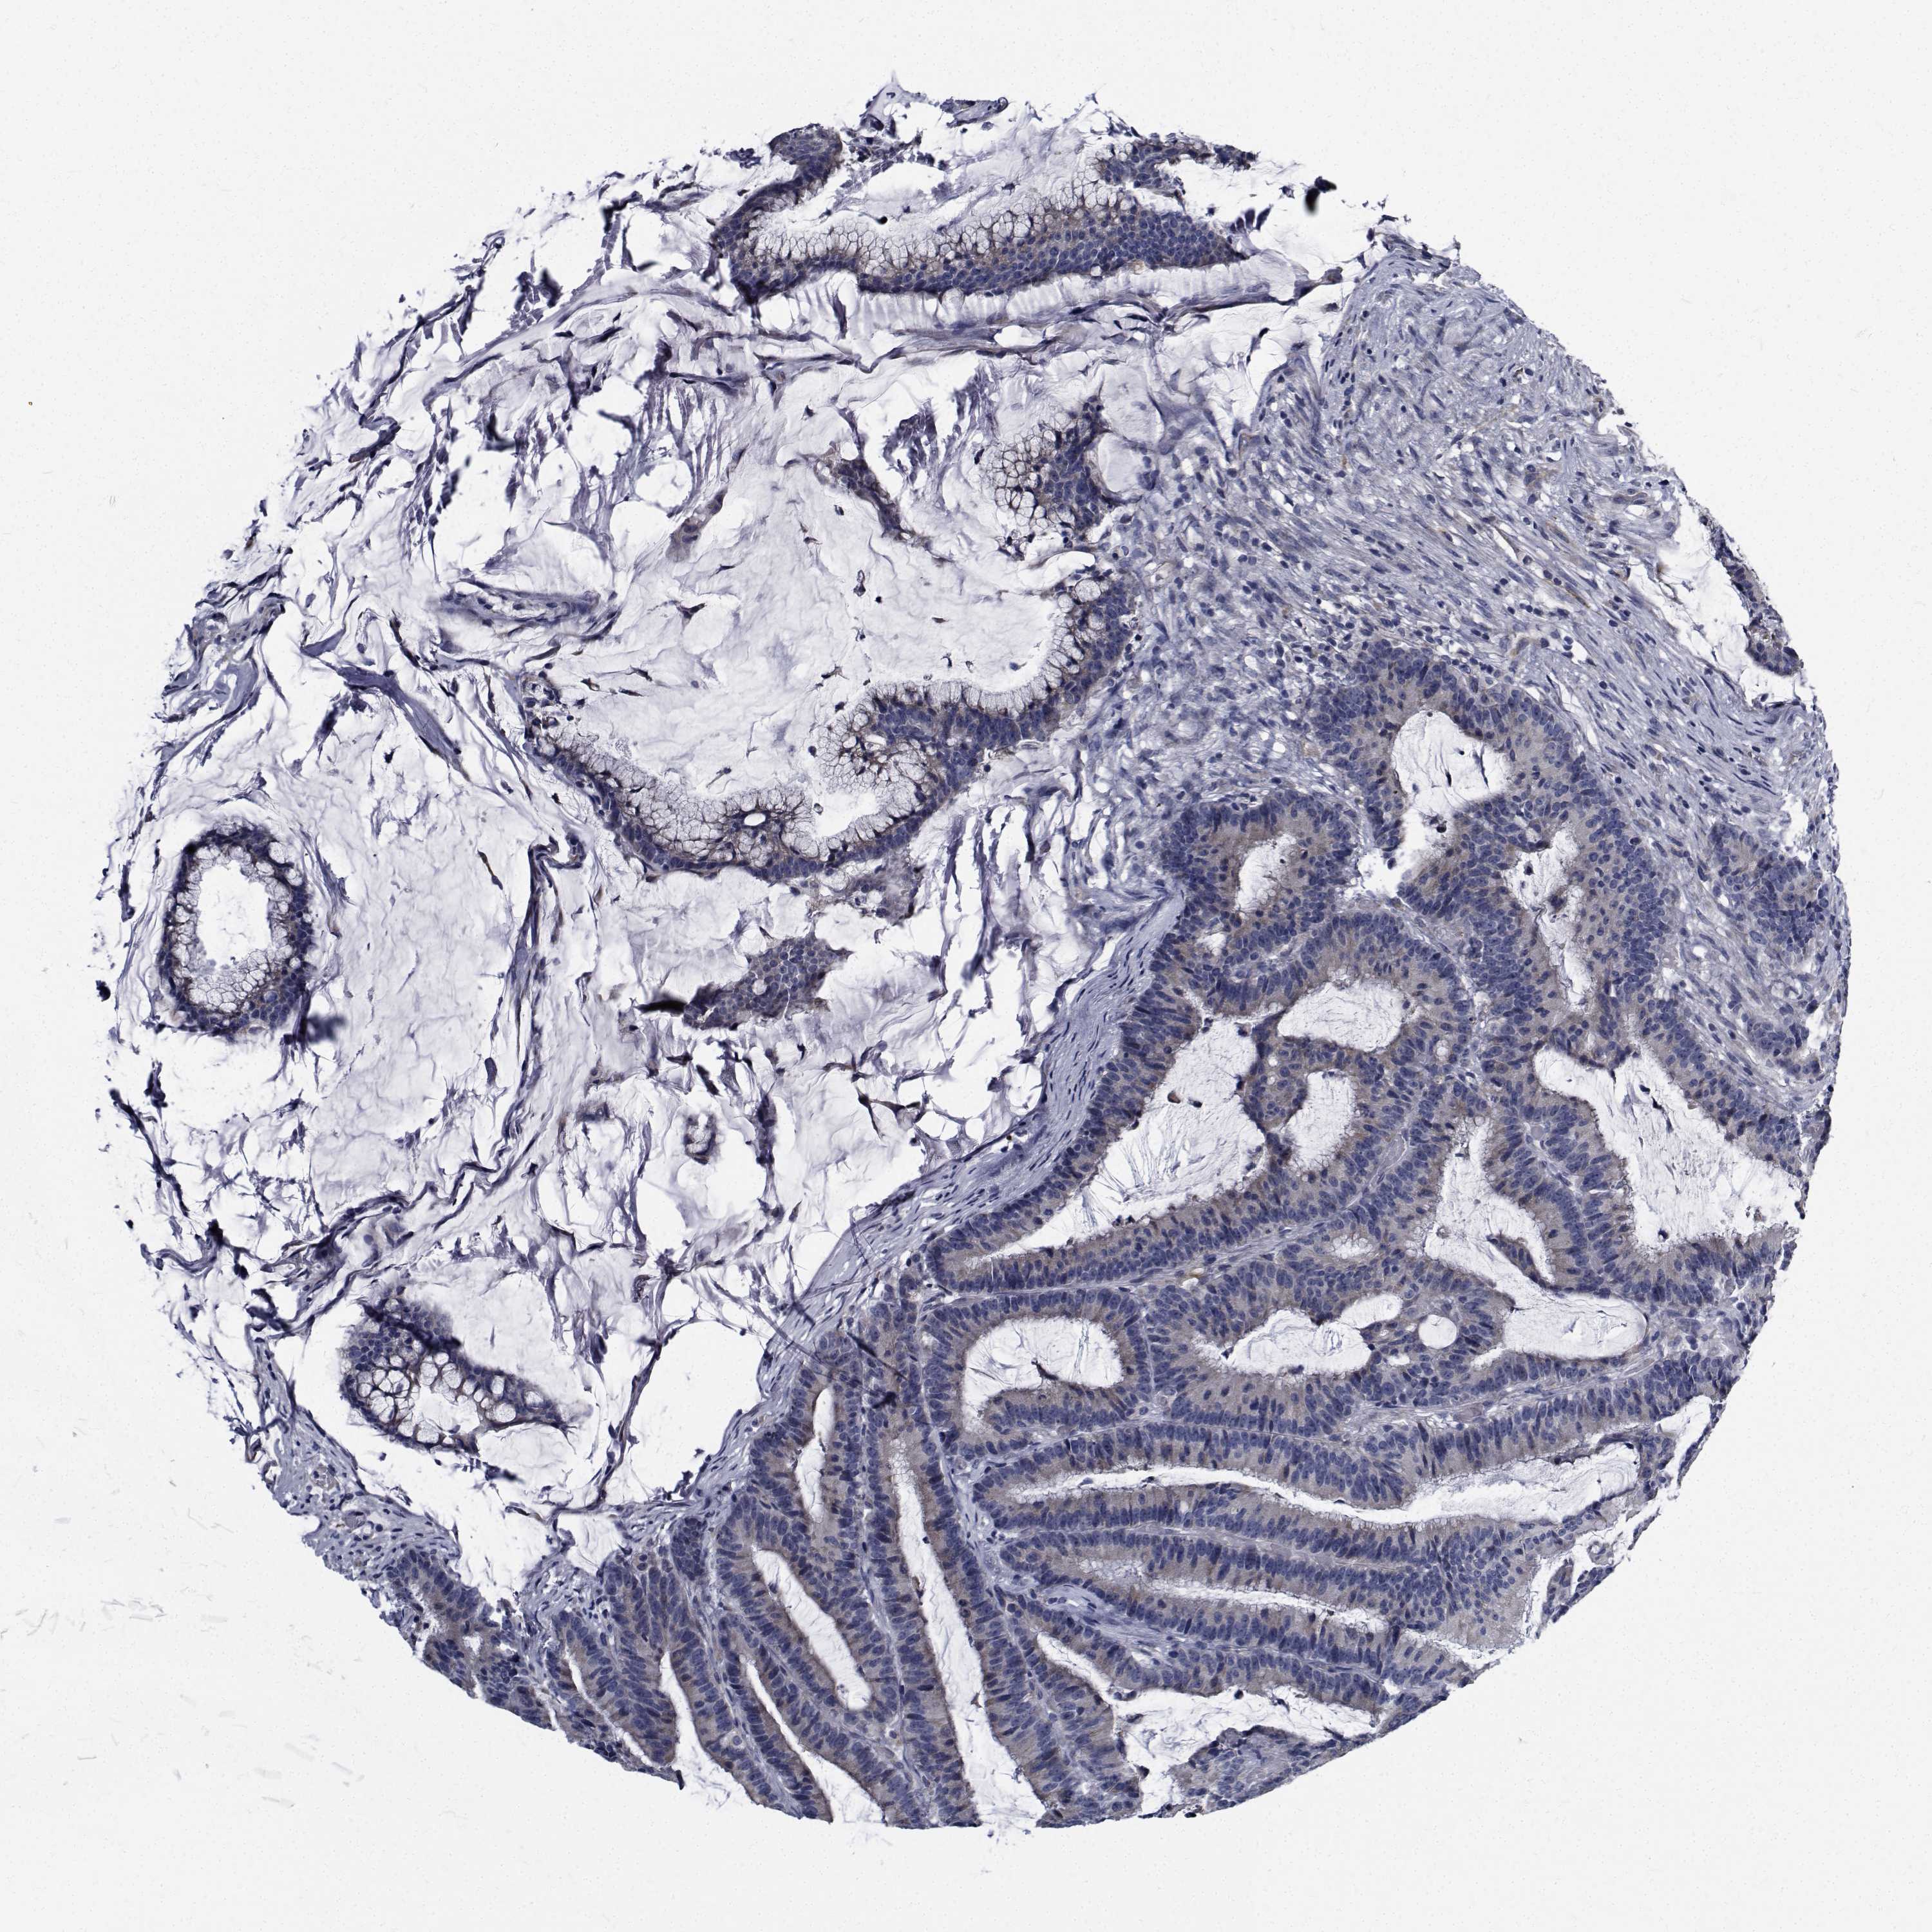

CANCER COLORECTAL CANCER Show tissue menu

Colorectal cancer

Human cancer

Colon adenocarcinoma